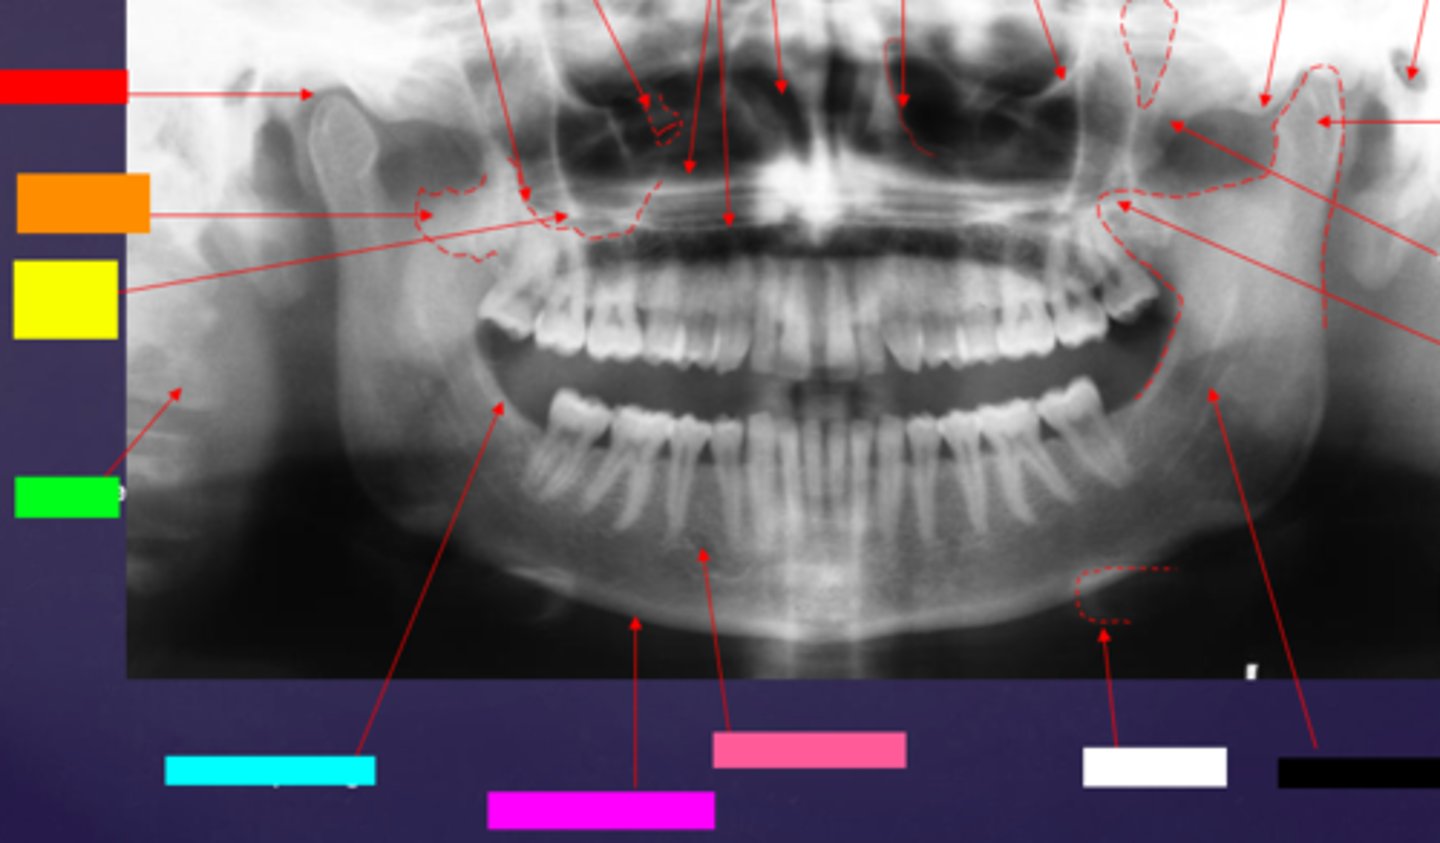

ID the hard tissue anatomy indicated by the arrow pointing from the red box:

floor of max. sinus

ID the hard tissue anatomy indicated by the arrow pointing from the orange box:

infra orbital canal and foramen

ID the hard tissue anatomy indicated by the arrow pointing from the yellow box:

hard palate/floor of nasal fossa

ID the hard tissue anatomy indicated by the arrow pointing from the green box:

nasal fossa

ID the hard tissue anatomy indicated by the arrow pointing from the light blue box:

ant. wall of max. sinus

ID the hard tissue anatomy indicated by the arrow pointing from the dark blue box:

coronoid process

ID the hard tissue anatomy indicated by the arrow pointing from the hot pink box:

infra orbital rim

ID the hard tissue anatomy indicated by the arrow pointing from the pink/salmon box:

pterygomaxillary fissure

ID the hard tissue anatomy indicated by the arrow pointing from the brown box:

external auditory meatus/ear canal

ID the hard tissue anatomy indicated by the arrow pointing from the white box:

articular eminence

ID the hard tissue anatomy indicated by the arrow pointing from the black box:

mandibular condyle

ID the hard tissue anatomy indicated by the arrow pointing from the gray box:

zygomatic bone

mandibular fossa

lateral pterygoid plate

zygomatic process of maxilla

cervical spine

external oblique ridge

inferior boarder of the mandible

mental foramen

inferior alveolar canal

hyoid bone